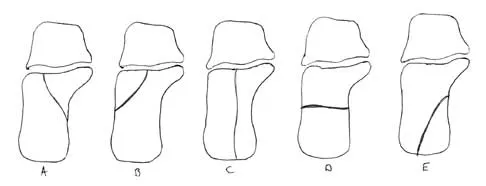

In Figure 14, the primary fracture line in a calcaneal fracture is best depicted by which of the following schematics?